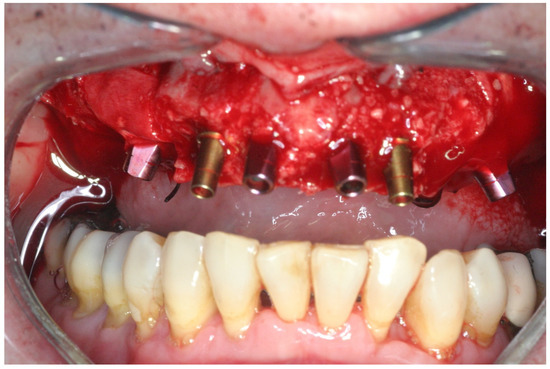

2.2. Surgical Treatment